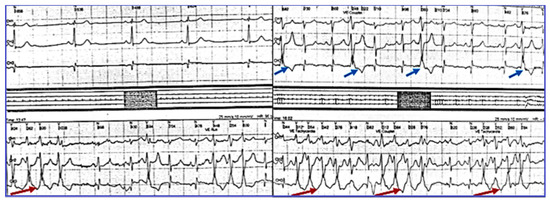

2.2. Diagnostic of SSS and Pacemaker Implantation

2.3. Evaluation of VA, Antiarrhythmic Therapy with Amiodarone and Secondary Effects